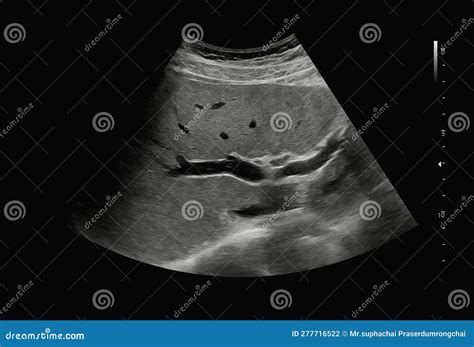

• Liver and Gallbladder Issues: Evaluating the size, shape, and structure of the liver and gallbladder to detect conditions such as gallstones, liver disease, and tumors.

After the ultrasound of the abdomen is completed, the images are reviewed by a radiologist who specializes in interpreting ultrasound results. The radiologist will look for any abnormalities or signs of disease in the abdominal organs and provide a detailed report to the referring physician. The results of the ultrasound can help guide further diagnostic tests or treatment plans.

It is important to note that while an ultrasound of the abdomen is a valuable diagnostic tool, it may not always provide a definitive diagnosis. In some cases, additional imaging tests such as CT scans or MRIs may be recommended to obtain more detailed information.